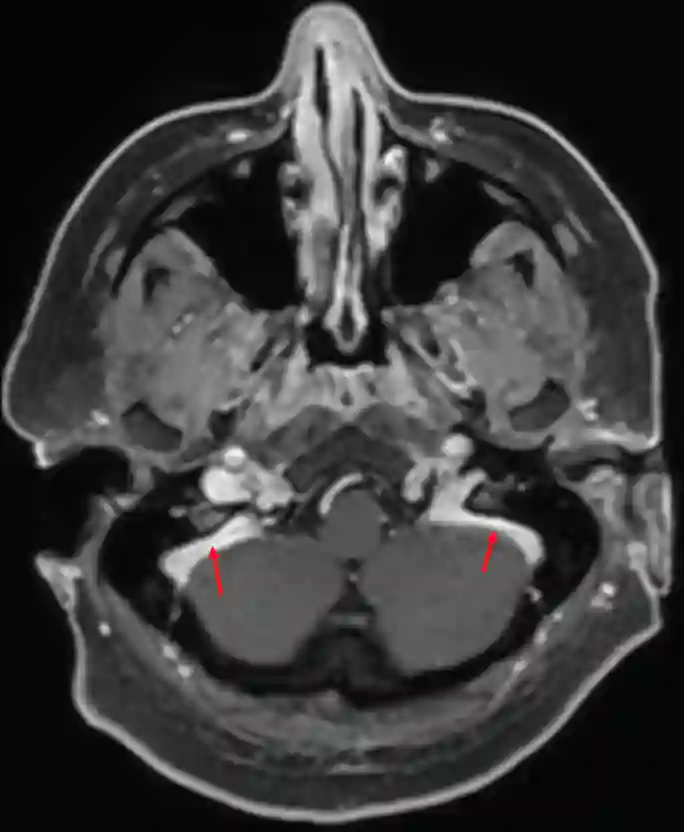

Sinus sigmoideus im MRI

Sinus sigmoideus (roter Pfeil) im axialen MRI (T1 Sequenz mit Kontrastmittel).